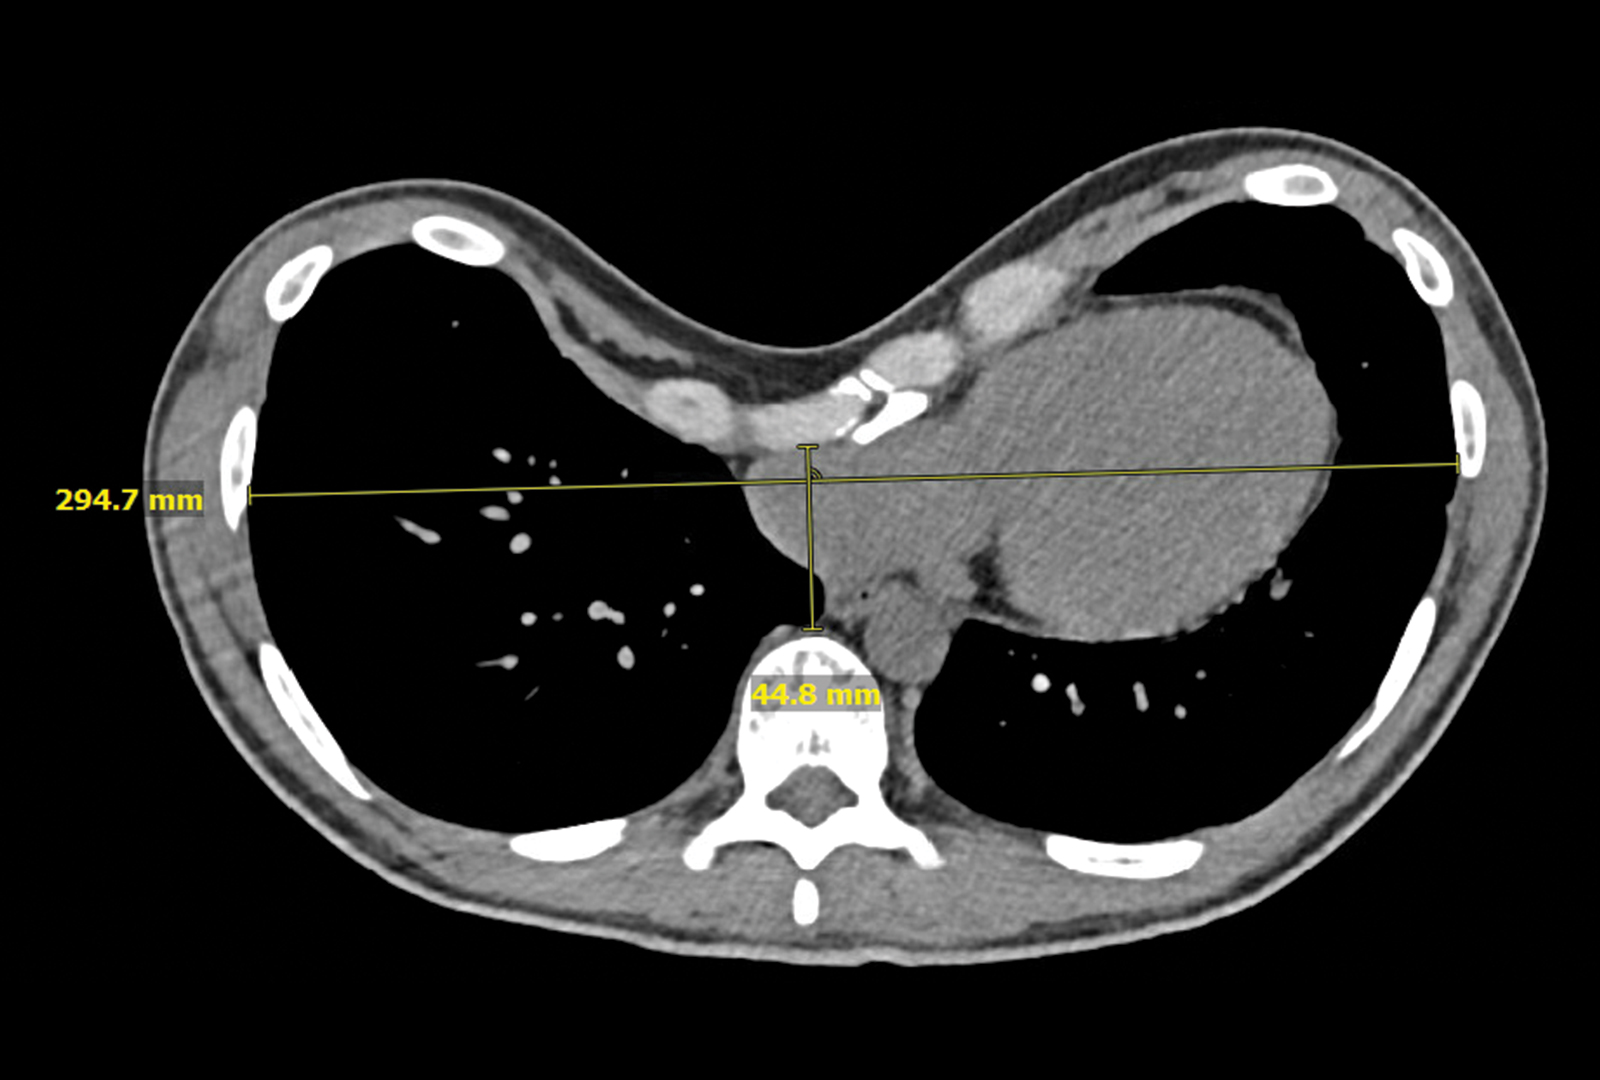

Preoperative chest CT of the patient’s pectus excavatum. Source: NYU Langone Health

The patient was reporting intermittent palpitations, chest pain, worsening shortness of breath with activity, and decreased exercise tolerance. “With a Haller Index of 6.5, the severity of the chest deformity was compressing the patient’s right atrium and ventricle, and limiting full lung expansion,” Dr. Bizekis says.

After carefully reviewing the patient’s chest CT imaging, he recommended the minimally invasive Nuss procedure.